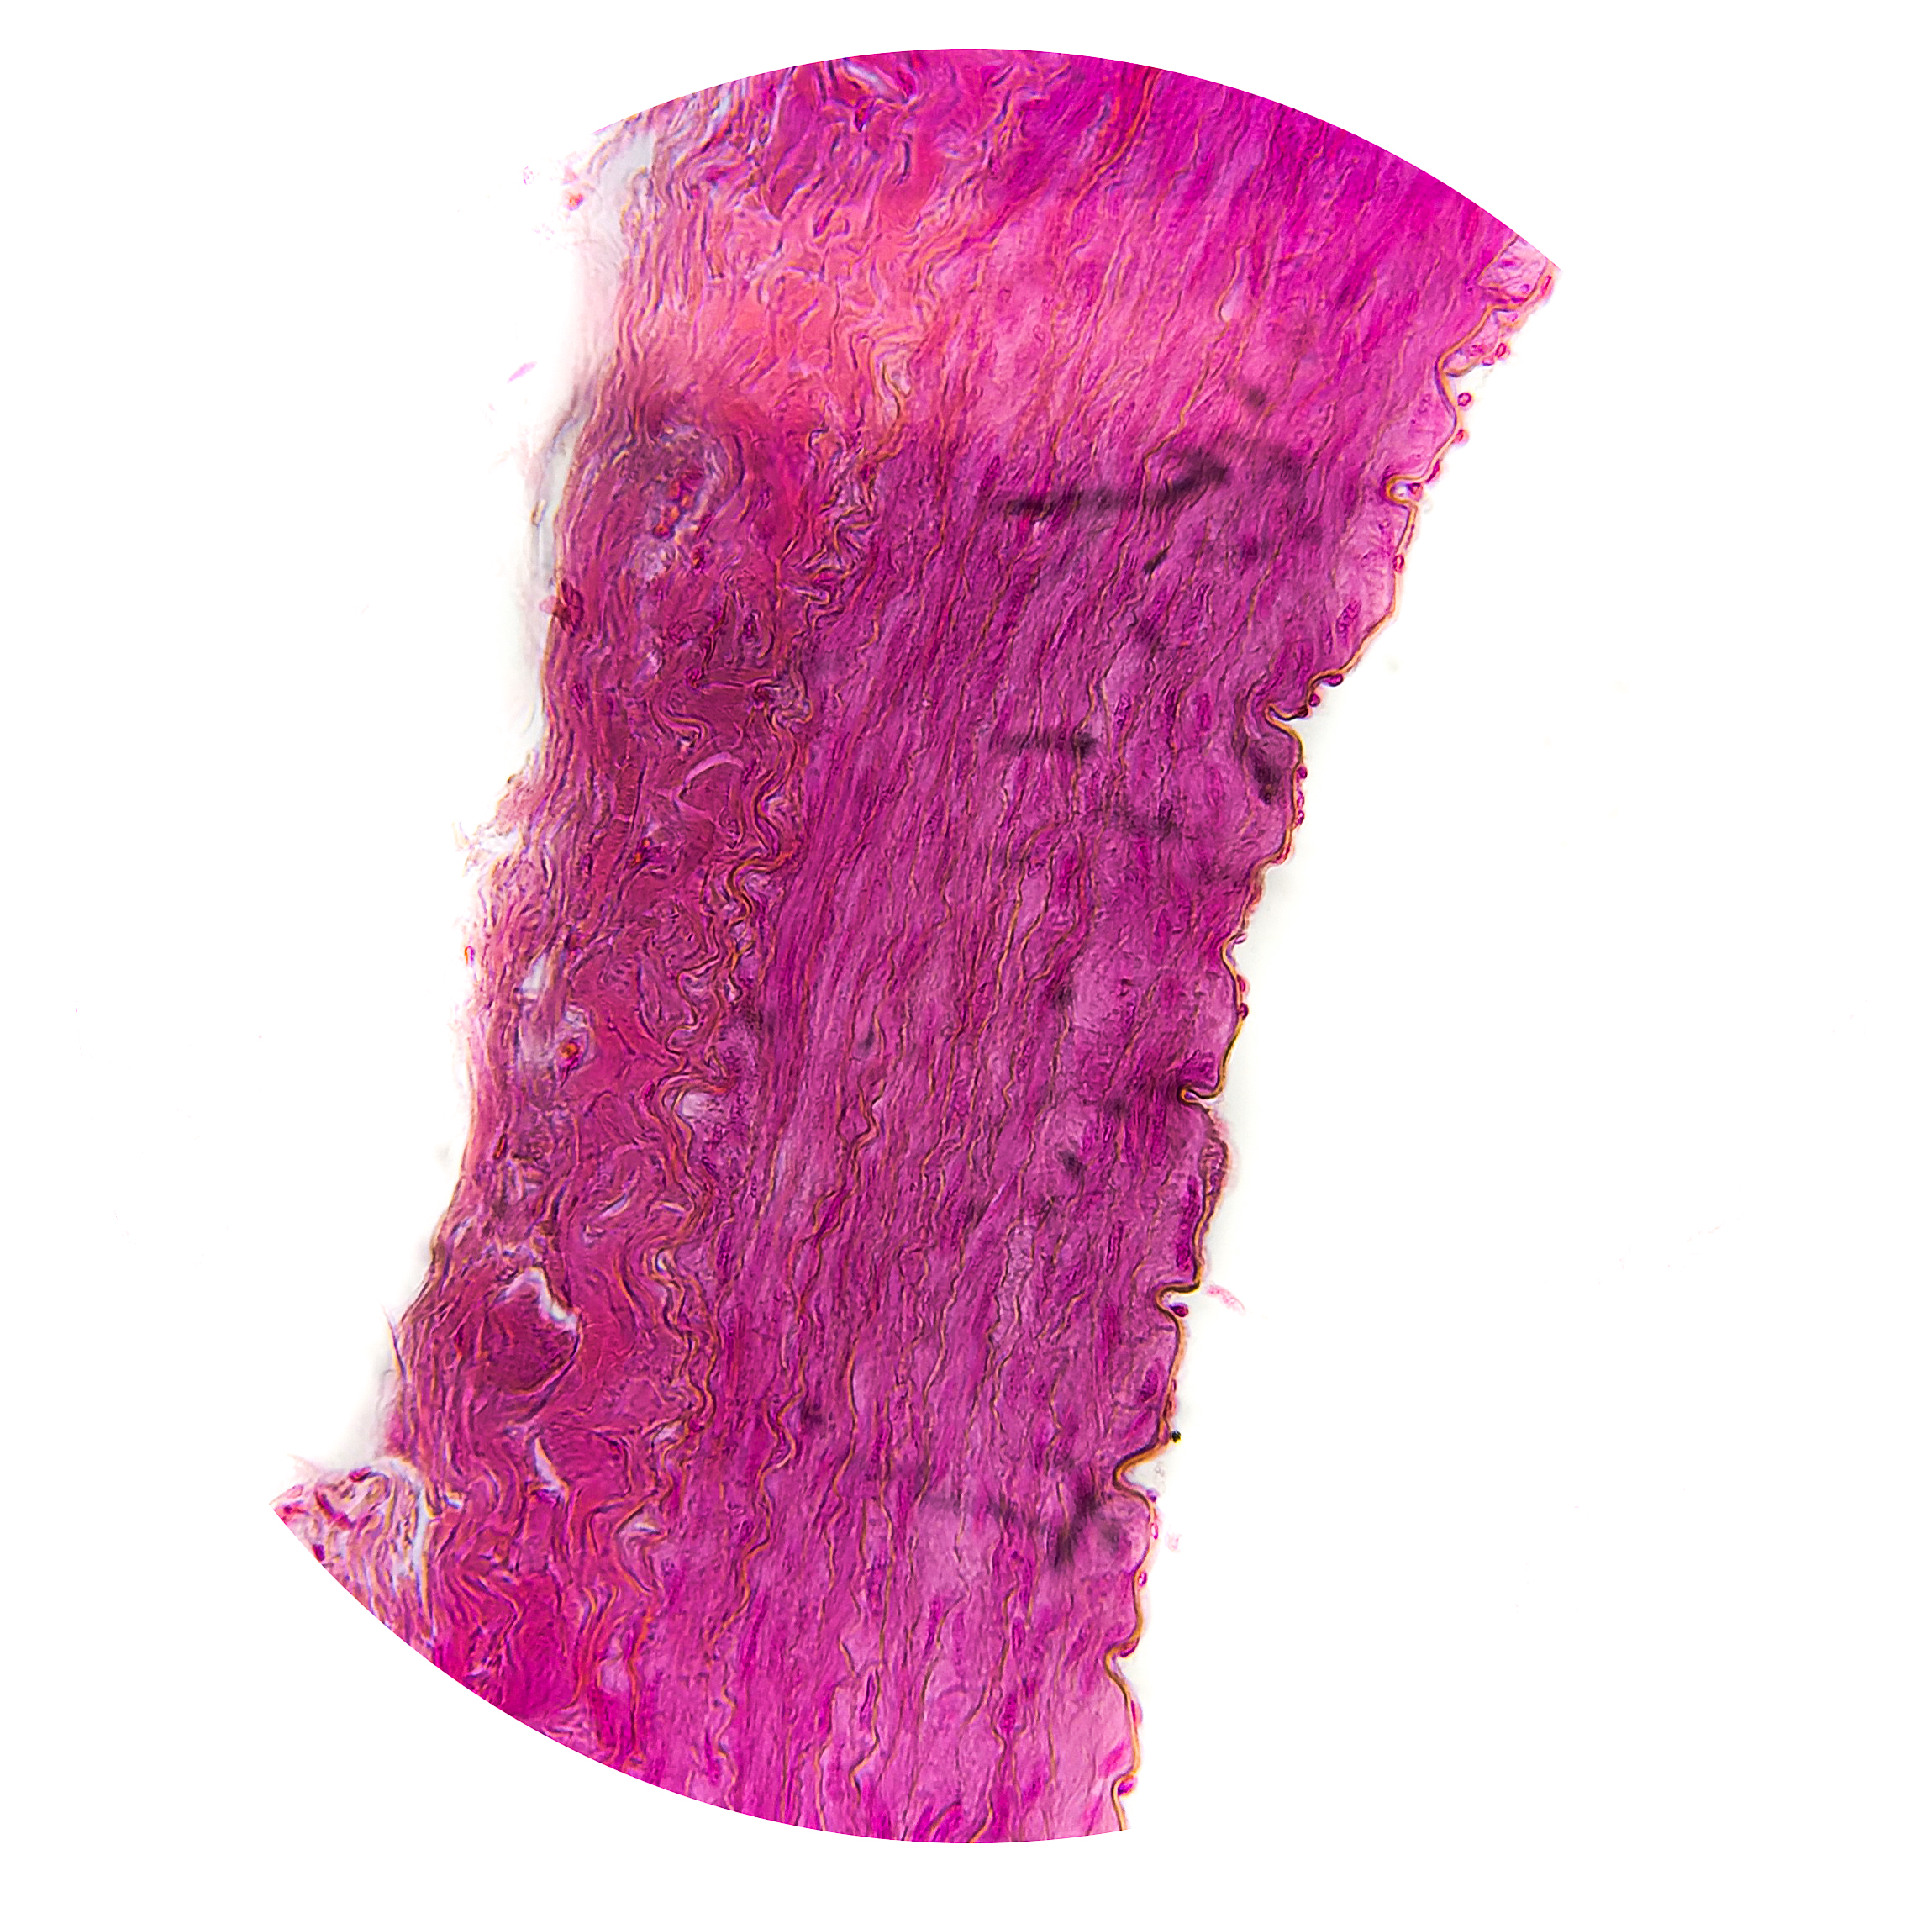

Muscular Arteries | Distributing

1. Tunica Intima

Endothelial layer

Subendothelial Connective Tissue | thinner than elastic arteries

Internal Elastic Lamina | distinct, may be bifid

2. Tunica Media

Layers of Elastic Fibres | 4 (small arteries) – 40 (larger arteries)

Layers of circular smooth muscle cells, elastic fibres, and type III collagen

External Lamina | present

Vasa Vasorum | may be present

3. Tunica Adventitia

Fibroblasts, type I collagen, and elastic fibres

Vasa vasorum, nervi vasorum